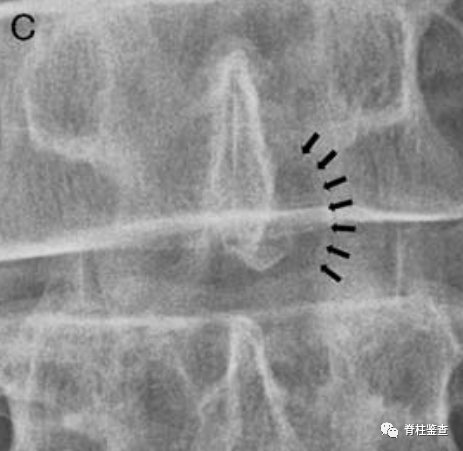

上次手术的椎板切除使此次手术无需进一步切除椎板(黑色↓)